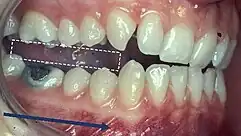

Classification of occlusion and malocclusion plays an important role in diagnosis and treatment planning in orthodontics. In order to describe the relationship of the maxillary molars to the mandibular molars, the Angle’s classification of malocclusion has commonly been used for many years.[8] This system has also been adapted in an attempt to classify the relationship between the incisors of the two arches.[9]

When discussing the occlusion of the posterior teeth, the classification refers to the first molars and may be divided into three categories:

- Class I: The mandibular first molar occludes mesially to the maxillary first molar, with the mesiobuccal cusp of maxillary first molar occluding in the buccal groove of mandibular first molar

- Class II: The mesiobuccal cusp of the maxillary first molar occludes anterior to the buccal groove of the mandibular first molar

- Class III: If the mesiobuccal cusp of the maxillary first molar occludes posterior to the buccal groove of the mandibular first molar[8]

Any deviation from the normal relation of teeth (Class I) is considered a malocclusion.

Class I relationships are thought to be “ideal”, however this classification does not take into consideration the positions of the two TMJ’s . Class II and III molar and incisor relationships are thought to be forms of malocclusion, however not all of these are severe enough to require orthodontic treatment. The Index of Orthodontic Treatment Need is a system that attempts to rank malocclusions in terms of significance of various occlusal traits and perceived aesthetic impairment.[11] The index identifies those who would benefit most from orthodontic treatment and onward referral to an orthodontist.